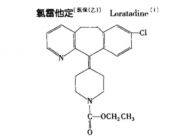

| 2021年7月26日 (一) 20:01 | 氯雷他定结构式.jpg (文件) |  |

15 KB | 77921020 | Uploaded with SimpleBatchUpload | 3 |